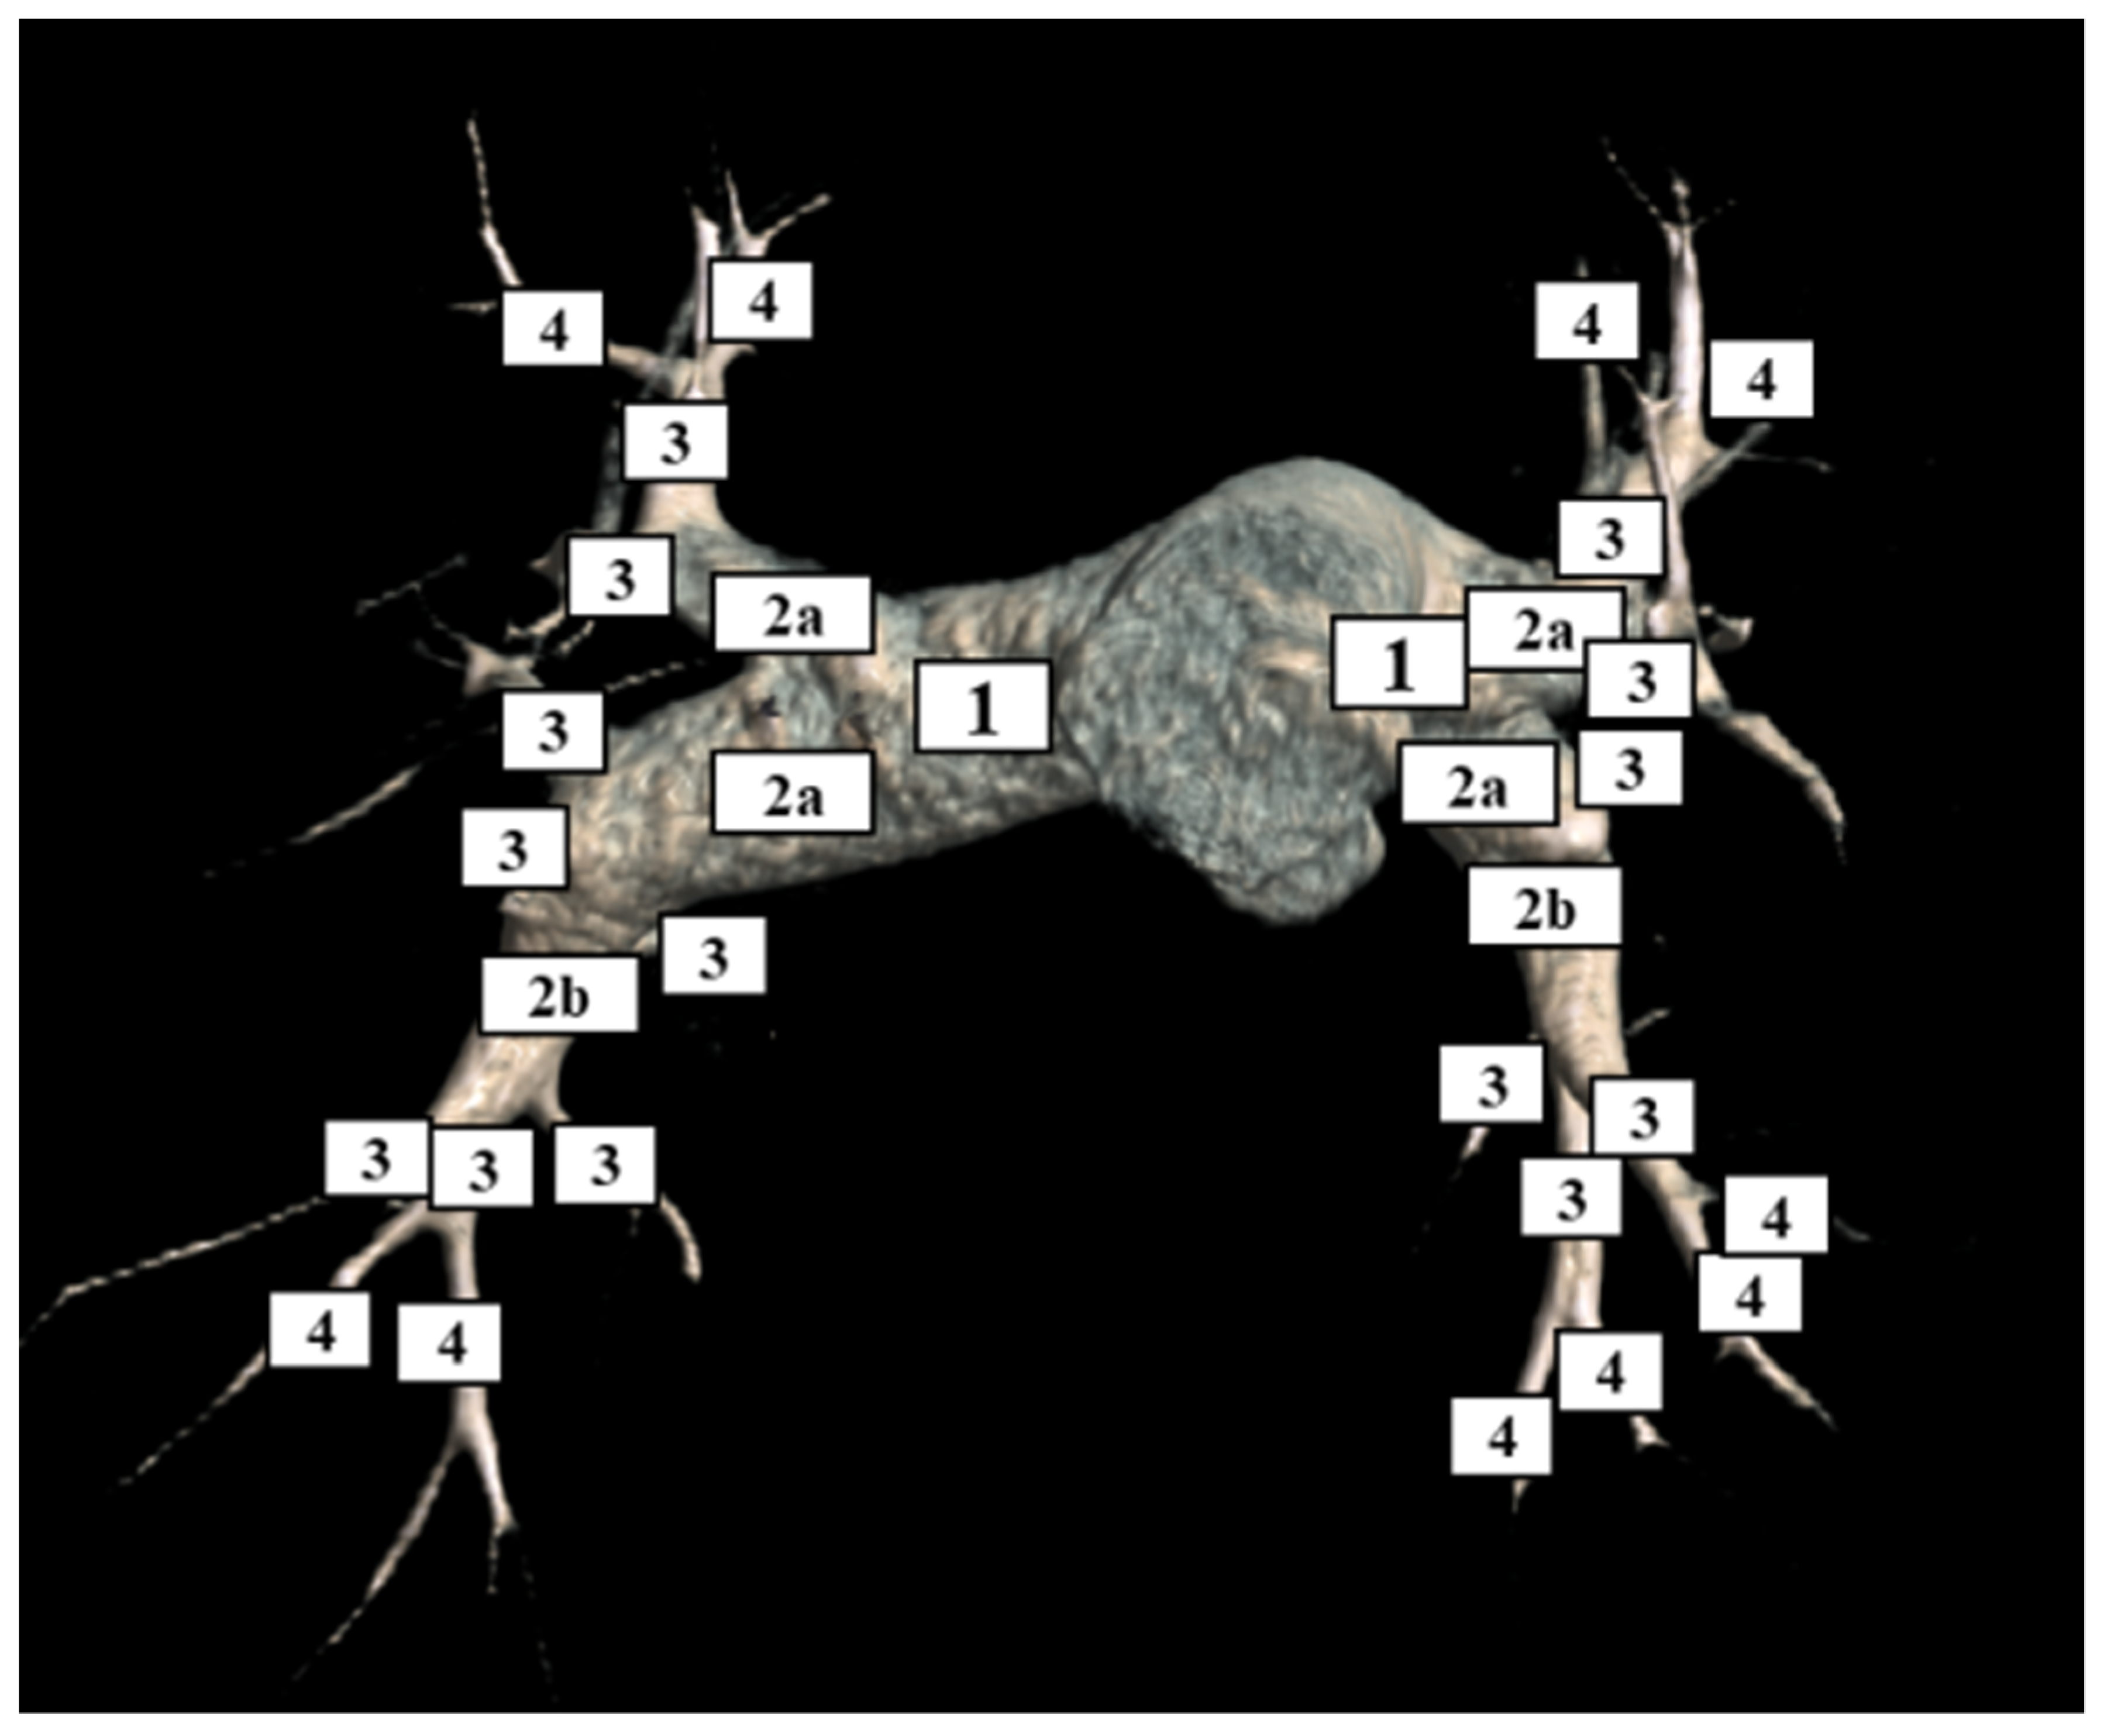

2.3. Analysis of Pulmonary Arteries

3.2. CT Categorization of Thromboembolic Level of Disease

3.2.2. Consensus Classification